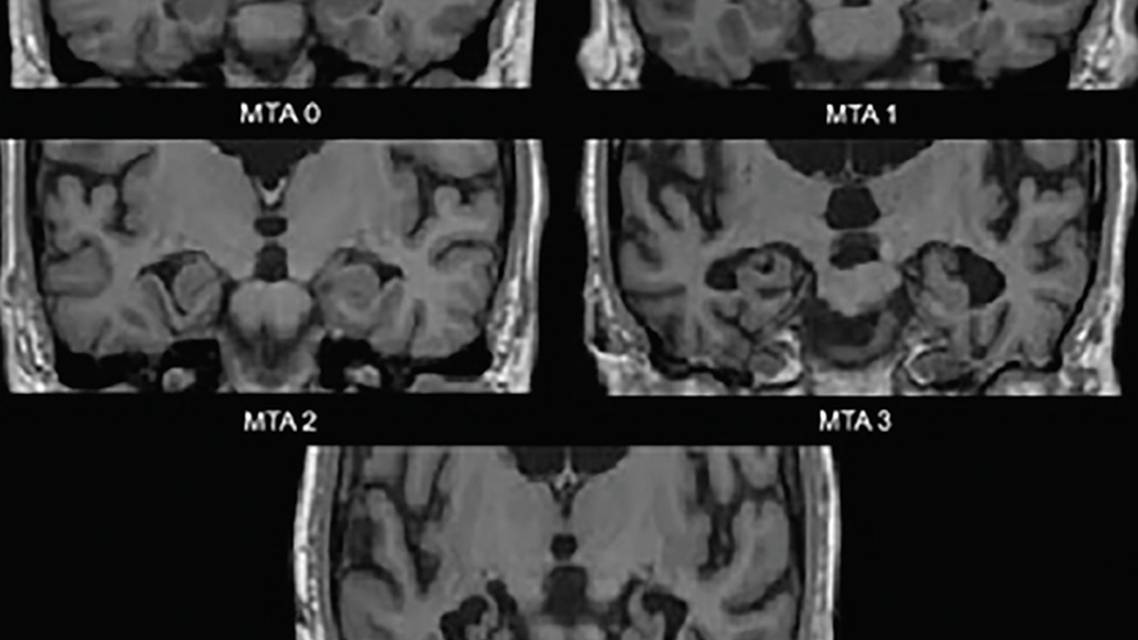

The earliest neurodegenerative changes in AD occur in the medial temporal lobes–the hippocampus, entorhinal cortex, and parahippocampal gyrus. As atrophy sets in, the choroid fissure and temporal horn of the lateral ventricle become dilated; these changes are best assessed in the coronal plane. A commonly used visual assessment scale based on these structures–the medial temporal atrophy (MTA) scale (Figure 1)–has been clinically3 and neuropathologically4 validated. Various studies using this scale or the structures it assesses have shown significant ability to discriminate people with AD from age-matched controls4 or those with DLB4 or vascular cognitive impairment (VCI).5 Medial temporal atrophy is also predictive of conversion from amnestic mild cognitive impairment (MCI) to Alzheimer’s dementia.3